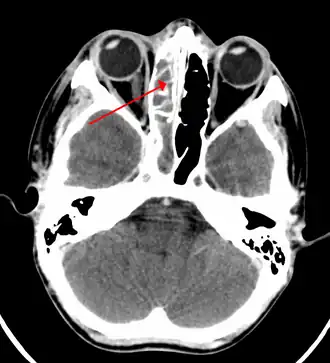

| TAC de sinusite na extremidade do seio etimóide | |